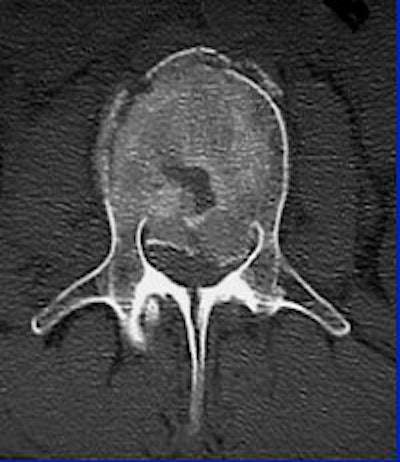

![]() ![]() |

"With CT, you see that it's not just a compression fracture of the superior endplate, but really it's a burst fracture involving the anterior, middle, and posterior columns. The fracture goes through the vertebral body (with) retropulsion of bone, and it goes through the spinous process, through the lamina, and even into the facet joint."